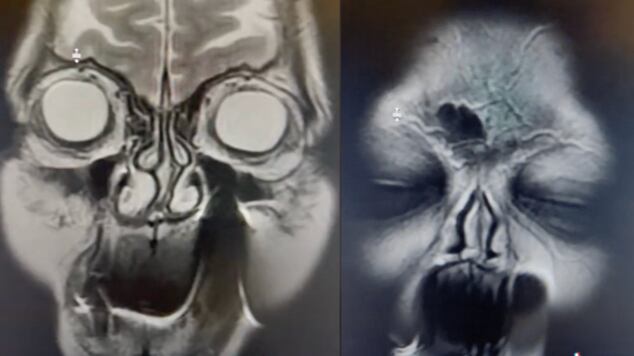

TikTok da para todo y para todos y esta vez un video encendió las alarmas terroríficas, y nada menos, que con una resonancia magnética de una mujer, que utilizó una aguja como palillo dental. Un radiólogo tiktoker subió la imagen a las redes, que ha llamado la atención de miles por su apariencia demoníaca.

Luis A Mayora, @luismayorgaoficial en la plataforma, compartió las imágenes del examen, en el que pareciera aparecer el diablo.

La punta de la aguja se le quedó en la encía, por lo que el profesional pretendía advertir sobre el mal uso de accesorios para la higiene bucal...pero finalmente lo que logró fue asustar.